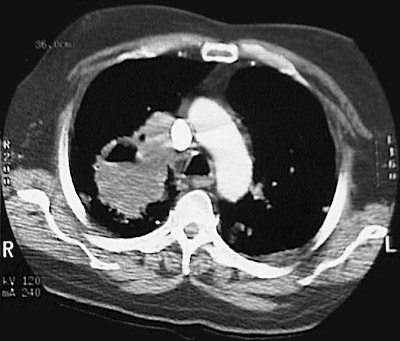

Click on the bronchogenic carcinoma in the CT scan above:

This chest CT scan demonstrates a large squamous cell carcinoma of the right upper lobe that extends around the right main bronchus and also invades into the mediastinum and involves hilar lymph nodes.